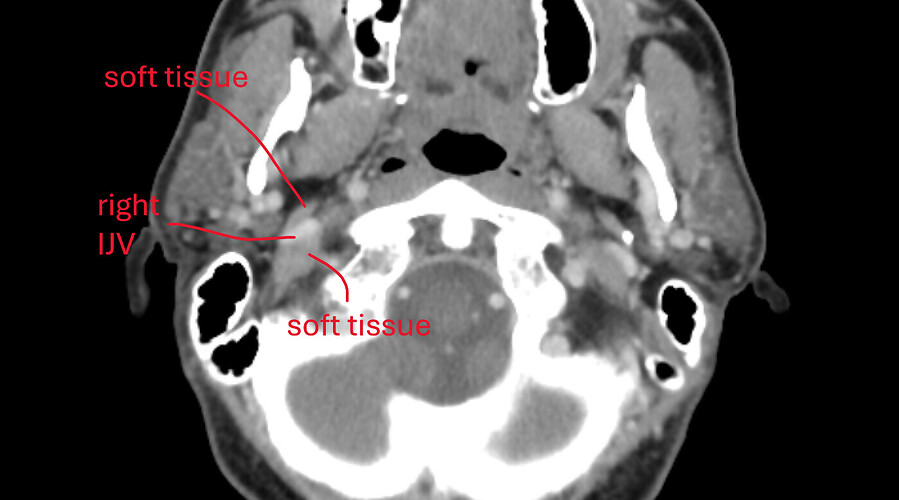

- Finally, my oral surgeon spotted something on the dental CBCT and asked me to check if I have ES. So, I did the CT for ES and it revealed a calcified portion of the stylohyoid ligament.

And, before we proceed, I literally looked at the 3D rendered CT today, and the calcified portion is only ~15mm, detached from styloid process, and about 1.5mm from C1. In the CT results, it says “partially calcified stylohyoid ligament, combined length 31mm” but the keyword there is “combined.”

I am also including some animated gifs of axial, sagittal, and coronal views of the calcification from the last CT scan.